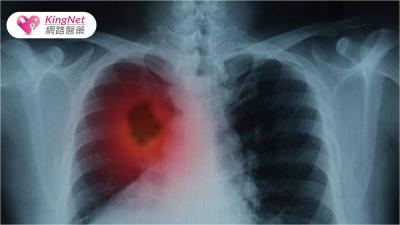

肺癌蟬聯十大癌症死因之首! 專家分析肺癌防治現況提出「三箭策略」

根據衛福部資料顯示,肺癌長年位居國人十大癌症死因之首,而且新發生人數也是十大癌症中最多的。由此可見,肺癌防治是目前非常重要的課題,若要達到「健康台灣」願景,這部...